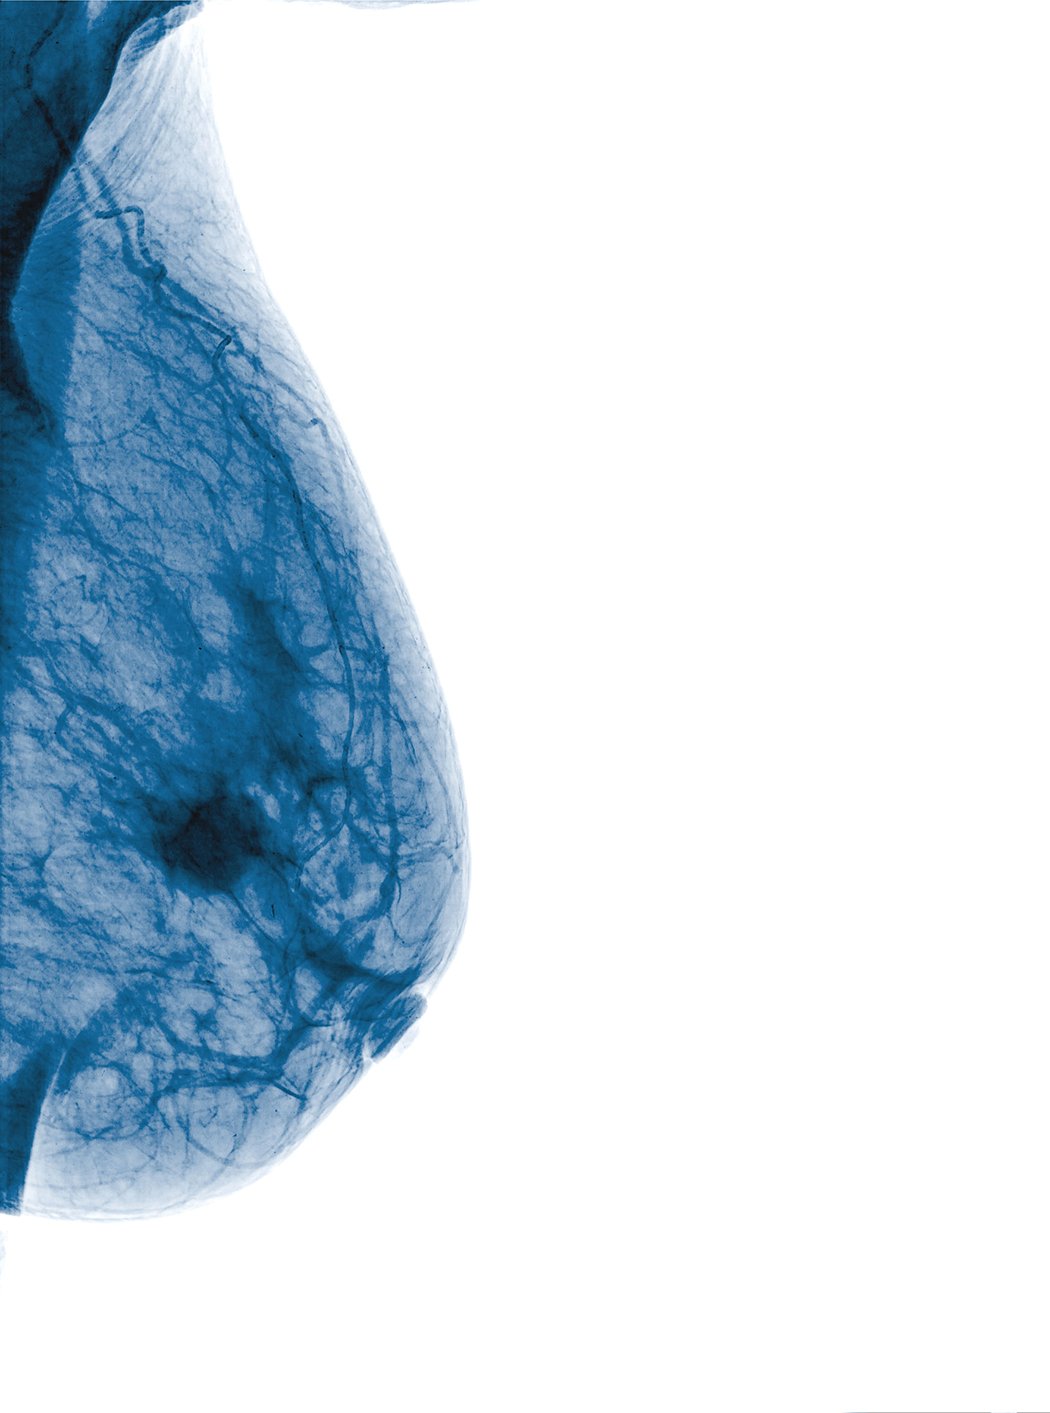

While mammograms play a vital role in efforts to identify breast cancer, they can present some challenges in women with dense breast tissue. Both dense breast tissue and cancer cells can appear as solid white in mammography, increasing the risk that results might be misinterpreted. Some recent advances in both technology and in communications about breast density have the potential to help clinicians and patients overcome these challenges in the years ahead.

An estimated 40 percent of women over age 40 have dense breasts, which have less fat and more connective, fibrous and glandular tissue compared to lower-density breast tissue. The risk of breast cancer is four to six times greater in women with extremely dense breasts than in women with low breast density,1 reinforcing the need for careful monitoring and effective communication about their risk.